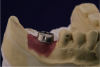

The case required placement of a tissue-level implant to restore the patient’s right mandibular first molar. A custom titanium abutment was fabricated with the margins just 0.5 mm above the gingiva to ensure that the area would be free of any retained cement (Figure 23). Figure 24 illustrates how the screw-access hole of the custom abutment was positioned slightly to the buccal. A decision was made to create a PFM crown that would be cemented to the custom abutment. However, the entire restoration would be screw-retained for future retrievability. The PFM that is fabricated for this type of restoration is a very thin coping that does not require a lot of space, is lightweight, and avoids a costly laboratory bill.

Fig 23. Custom titanium abutment in screw-cementable case.

Figure 23

Fig 24. Screw-access hole positioned slightly buccal.

Figure 24